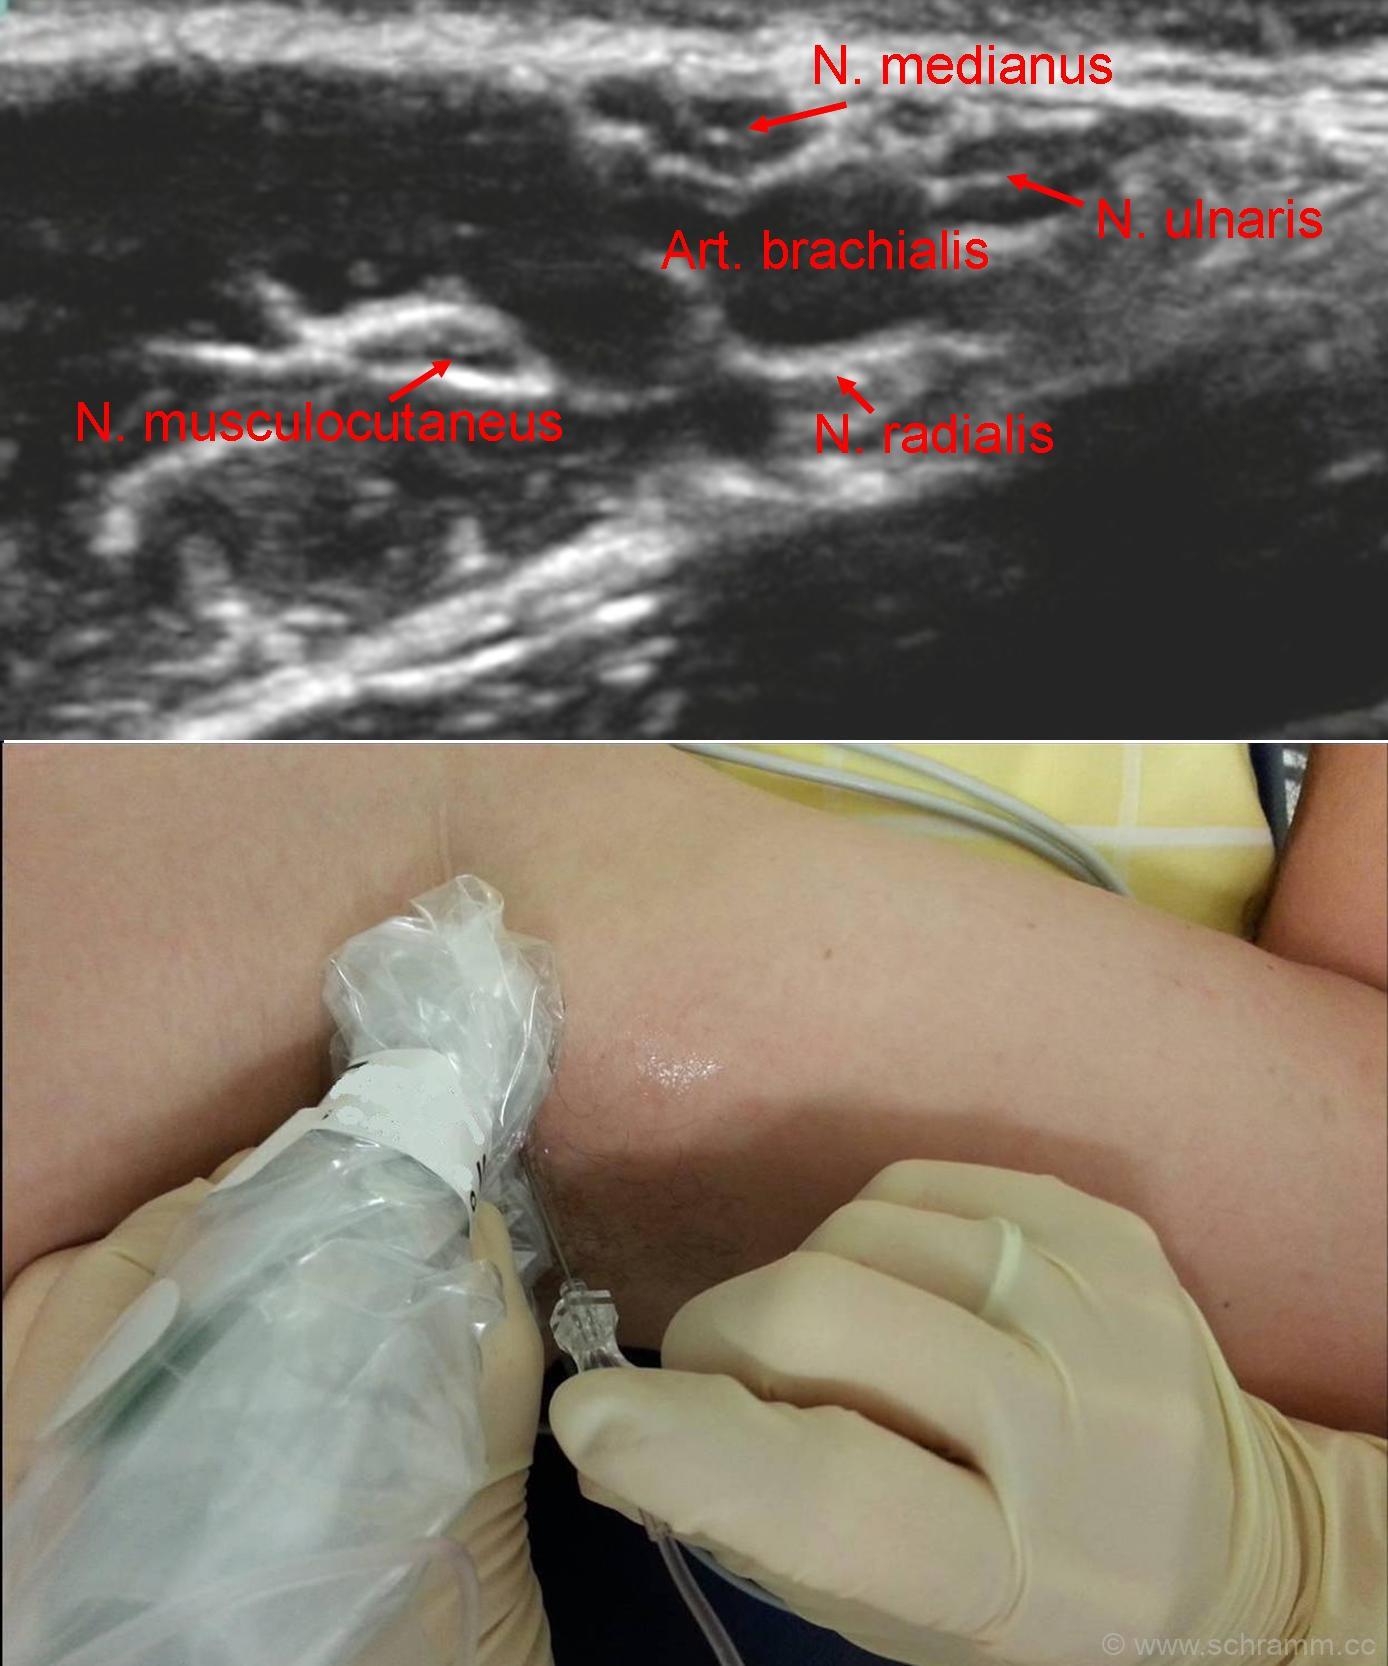

Die axilläre Plexusblockade ist eine Form der Regionalanästhesie. Durch die Injektion eines Lokalanästhetikums im Bereich der Achselhöhle werden die Nerven des Plexus brachialis (z.B. Nervus medianus, Nervus ulnaris, Nervus radialis, Nervus musculocutaneus) reversibel ausgeschaltet.

Der Patienten befindet sich zur Punktion in Rückenlage. Der Arm wird in der Schulter in Außenrotation um 90° abduziert und am Ellenbogen um 90° gebeugt. Die Punktion erfolgt aufgrund der hohen Sicherheit und geringeren Versagerrate ultraschallgestützt. Als Leitstrukturen dienen die Arteria axillaris und der kranial von ihn verlaufende Musculus coracobrachialis. Die Arteria axillaris wird in der Achsel palpiert und mit den Fingern fixiert. Der Einstich der Kanüle erfolgt unmittelbar ventral der fixierten Arterie und ca. einen QF distal der axillären Hautfalte.